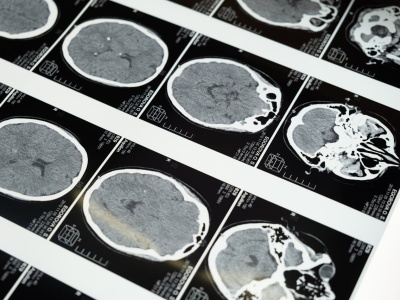

Badania pokazują, że menopauza zmienia strukturę mózgu kobiety – wpływa na pamięć, koncentrację i emocje. Jakie procesy za tym stoją? Artykuł Jak menopauza wpływa na strukturę i funkcje mózgu? Najnowsze badania 2025 pochodzi z serwisu Alert Medyczny.

Menopauza nie dotyczy tylko uderzeń gorąca i zmienności nastroju – badania Cambridge University pokazują, że wpływa również na strukturę mózgu, zwłaszcza w obszarach związanych z pamięcią i emocjami. Menopauza powoduje zmiany w mózgu Menopauza to ok...